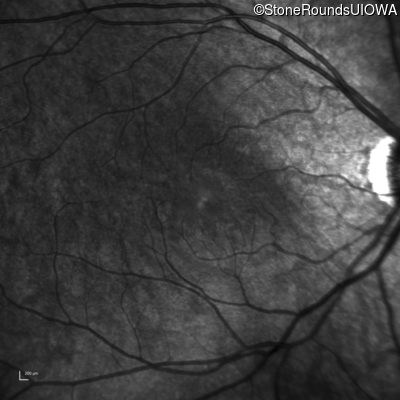

Infrared Fundus Photograph - Right - 20/40 +1

Exemplar